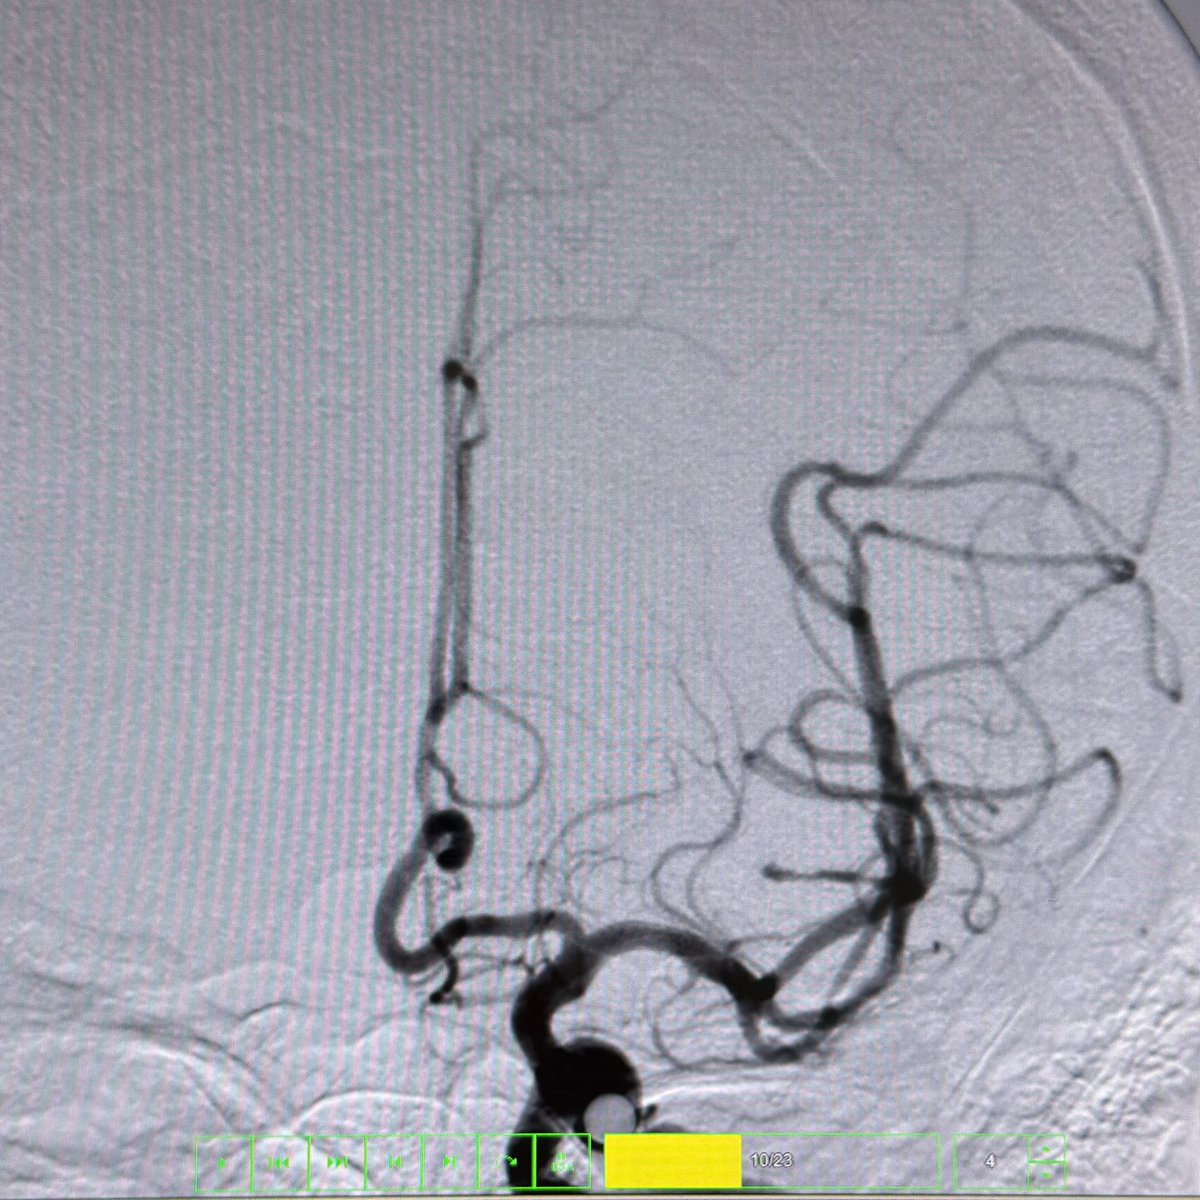

This 🧔♂️ presents with a subarachnoid haemorrhage in the left suprasellar cistern

DSA shows an infundibulum/ aneurysm of the left PCom. To coil or not was a conundrum. Every expert has a different take

The size is 3.4 mm x 2.6 and it is located in the region of the bleed.

What would you do?